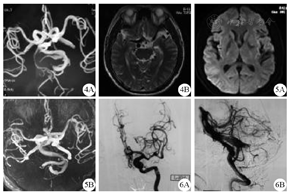

此后患者因头晕反复于本院神经内科门诊就诊,口服敏使朗疗效不佳,于2015年5月6日因头晕收入院。入院体检:血压210/120 mmHg,神经系统查体未见明显异常,头颅MRI+MRA检查结果见图4。予以控制血压对症治疗,于2015年5月11号好转出院。

MRI and MRA of the ptient(2015-05)

MRI and MRA of the patient (2015-09)

DSA of the patient (2015-09)

4A:头MRA示椎基底动脉扩张、迂曲,4B:头MRI示扩张、迂曲的椎基底动脉流空征明显;5A:双侧额顶叶多发脱髓鞘改变,左侧基底节区含铁血黄素沉积,5B:椎基底动脉异常增粗扩张,基底动脉内径超7.5 mm,脑干、小脑受压变形;6A:颈内动脉颈段迂曲,左侧颈内动脉交通段管腔膨大,大脑前、中动脉多个分支管腔扩张伴多发局限性狭窄,6B:右侧椎动脉颅内段"开窗",椎动脉颅内段、基底动脉及双侧大脑后动脉近段管腔明显迂曲扩张,血流缓慢

患者后因"视物重影,右眼睑下垂1个月"于2015年9月29日收治入本院神经外科。入院体检:血压210/175mmHg,神志清,言语清晰,双侧瞳孔等大正圆,直径约3 mm,对光反射灵敏,右眼睑下垂,右眼球外展位,内收受限,左眼球活动正常,余颅神经查体未见异常,四肢肌力5级,肌张力正常,腱反射正常,双侧病理征阴性。诊断为右侧动眼神经麻痹,高血压病3级。入院后头MRI+MRA检查结果见图5。为进一步排除右侧后交通动脉瘤可能,行DSA检查,具体结果见图6。考虑患者动眼神经麻痹为扩张的基底动脉压迫所致,予以控制血压,使用弥可保营养神经,对症治疗,患者于2015年10月11日症状完全缓解出院。